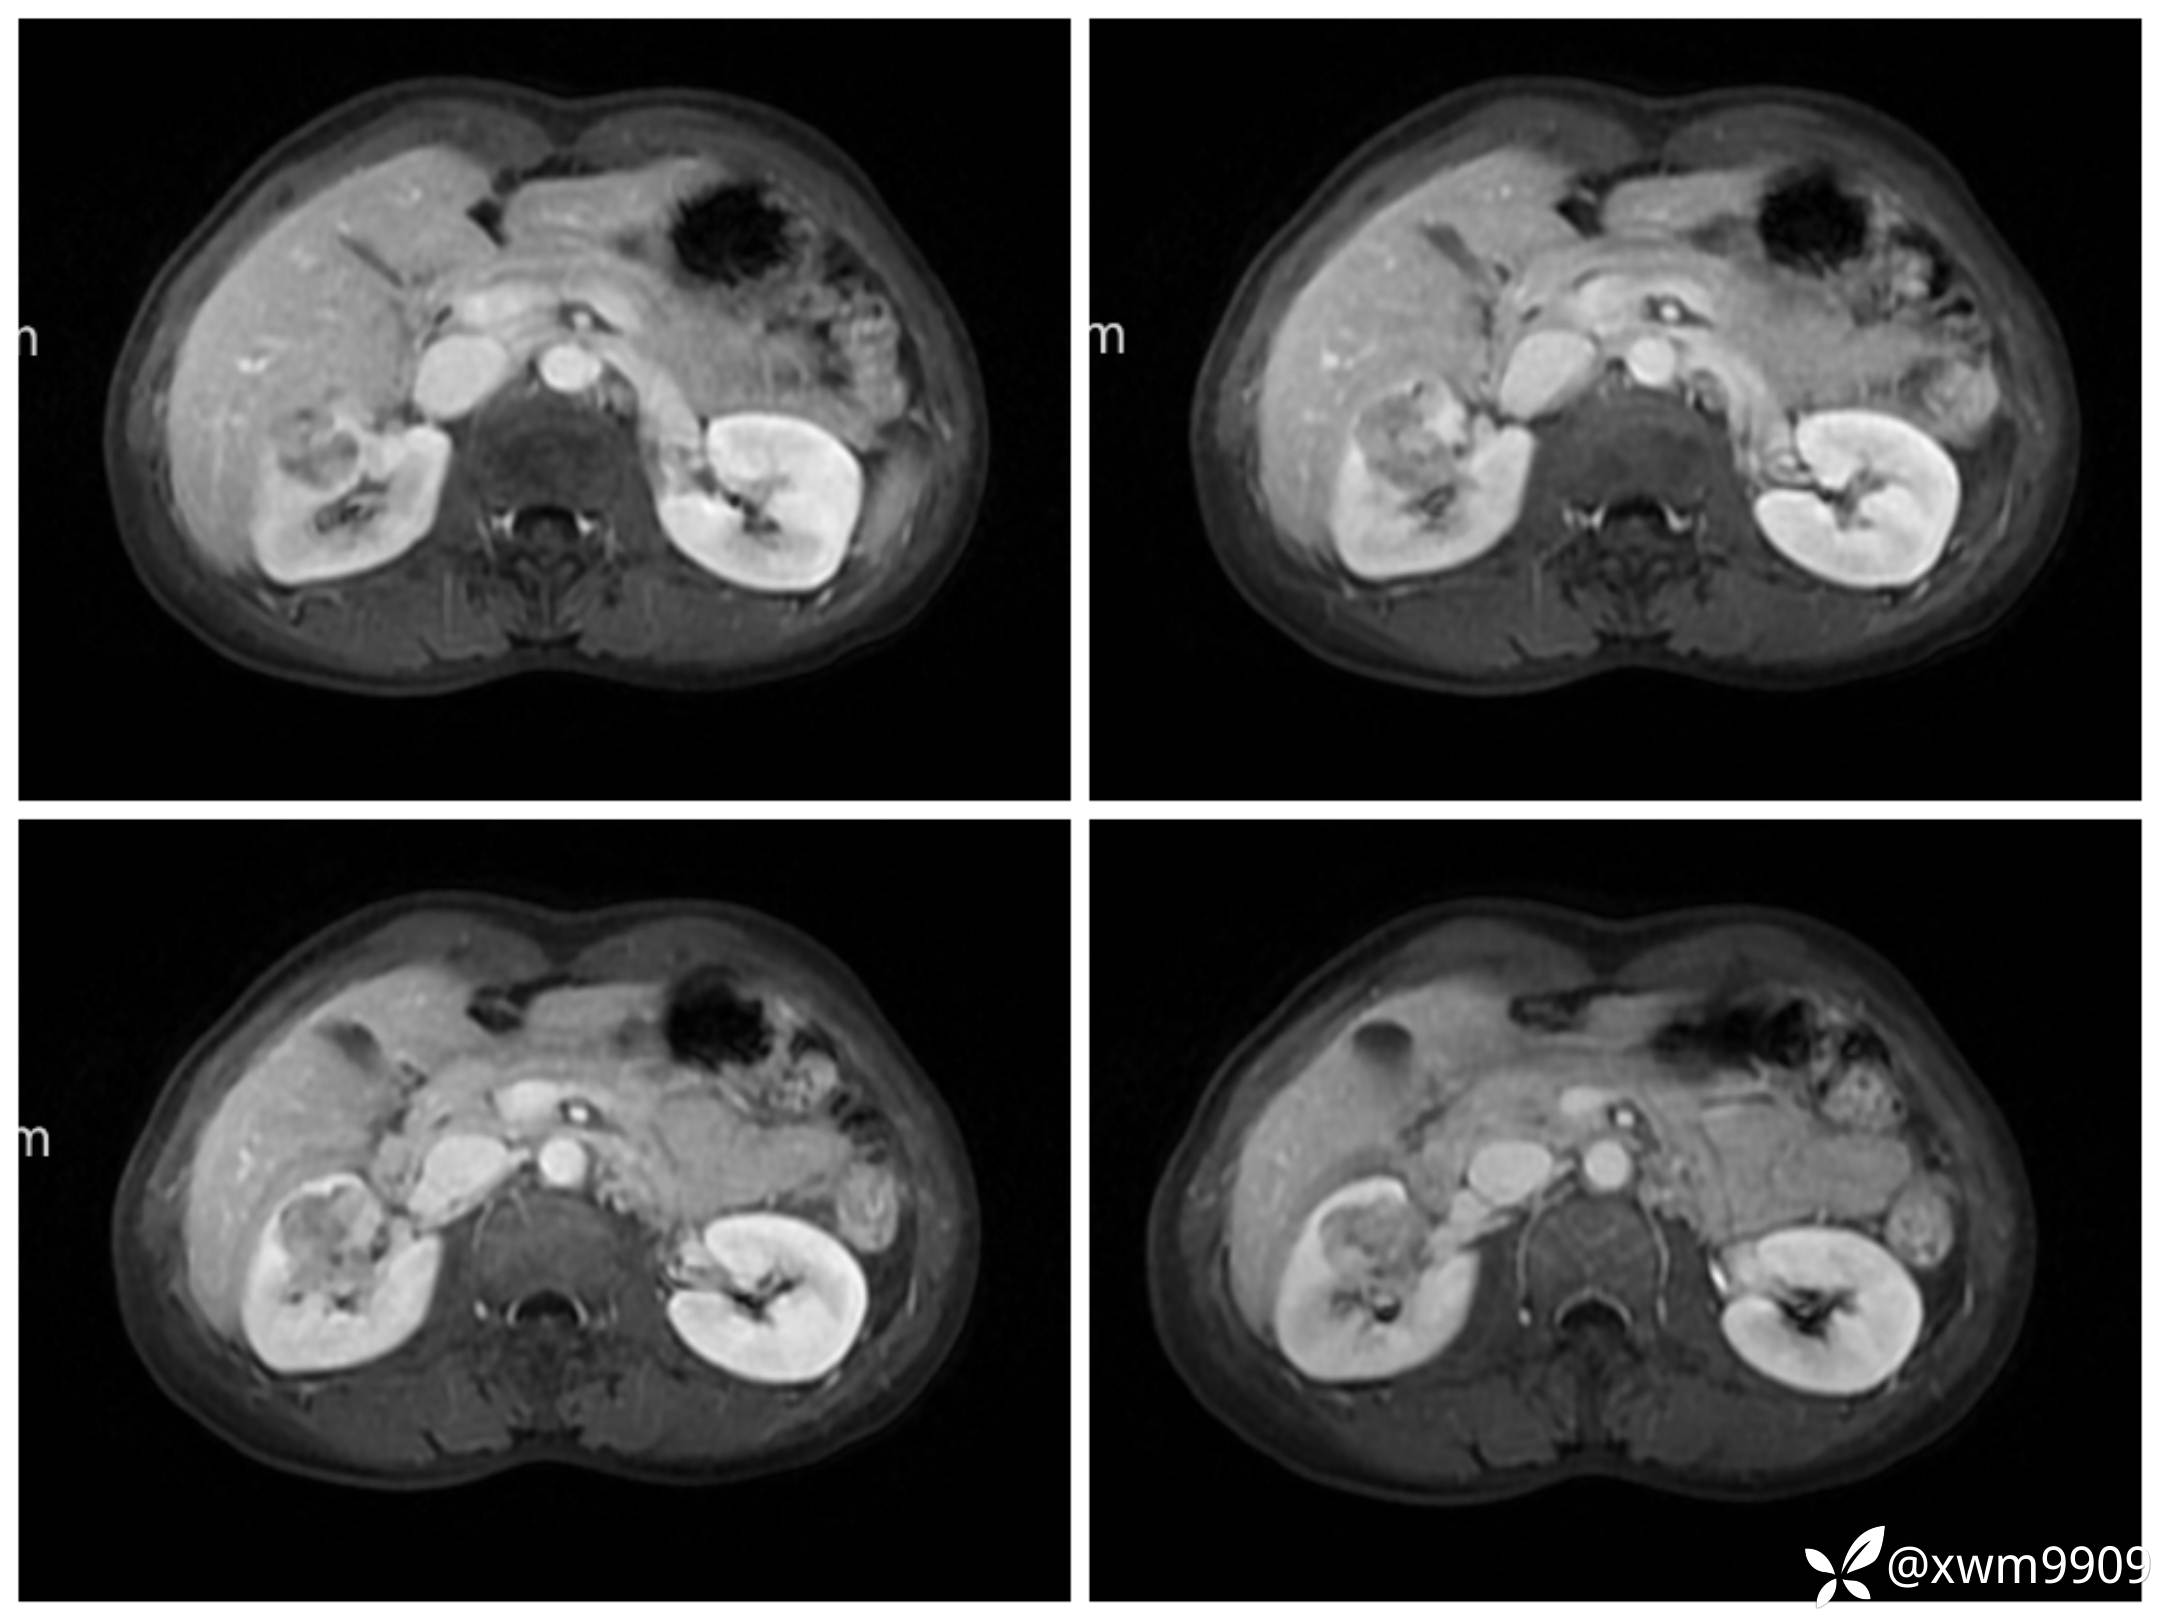

T2:

反相位:

同相位:

LAvA:

A:

v:

平衡期: